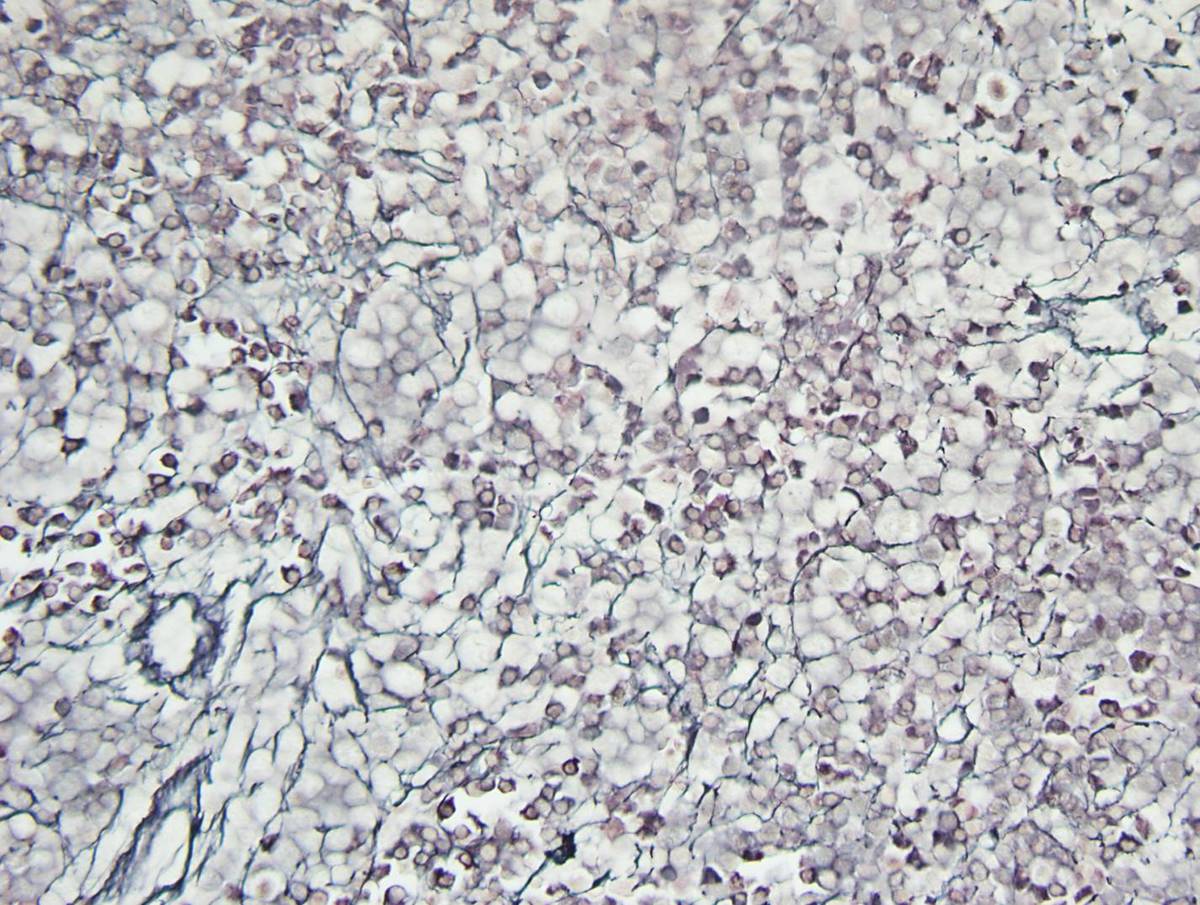

Bone Marrow Examination Bone marrow core needle biopsy (left posterior iliac crest) was fixed in Bouin solution. Bone marrow aspiration was sent for morphological evaluation, cytogenetic analysis and flow cytometry. • Core needle biopsy (hematoxylin and eosin) demonstrated marked erythroid hyperplasia, dyserytropoiesis and patchy interstitial pockets of large mononucleated cells with oval to folded nuclei, irregular nuclei contour and abundant amount of amphophilic cytoplasm. Moderate reticulin fibrosis was noted (MF-2, European Myelofibrosis Network) • Wright- Giemsa stained aspirate smear were of limited quality demonstrating 3% myeloblasts, promonocytes, atypical monocytes and erythroid hyperplasia with significant dyserythropoiesis. No Auer rods were present. Splenectomy Splenomegaly: 12.6 x 5.0 x 3.0 cm, 137 gms. Unremarkable capsular surface and homogenously red and congested parenchyma. Representative sections submitted for flow cytometry, cytogenetics, molecular studies and permanent sections (formalin fixed/ paraffin embedded). • Hematoxylin and eosin (H&E) stained slides showed expanded red pulp with extensive and markedly left-shifted extramedullary hematopoiesis (EMH) consisting of a mixture of left-shifted erythropoiesis, left-shifted myelopoiesis, occasional megakaryocytes and rare blast cells. White pulp appeared decreased and morphologically unremarkable. • Wright-Giemsa stained touch preparations show extramedullary hematopoiesis with erythroid predominance showing dysplastic features. Scattered blasts were present, promonocytes and monocytes including atypical forms were identified. Remaining myeloid elements showed progressive maturation

Bone Marrow Biopsy • IHC analysis: Blasts (3%) were positive for CD34, with a subset showing CD117 positivity. Marked erythroid hyperplasia was highlighted by E cadherin. • Flow cytometric analysis detected 1.1% myeloblasts, a minute population of hematogones and increased monocytes with a spectrum of maturation. Splenectomy • IHC analysis: CD34 highlighted rare blasts. CD61 highlighted rare megakaryocytes. Glycophorin A and E-cadherin showed erythroid elements. CD33/CD117 demonstrated left shifted myelopoiesis. CD20 demonstrated a relative decrease in white pulp. Increased CD56+ small lymphocytes were present. • Flow cytometric analysis detected immature precursor cells, as defined by CD34 or CD117 expression (3.4% and 6.1%, of gated events respectively).

| Spleen, 20X | ![]() |